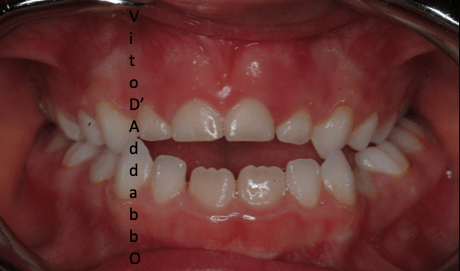

dopo – fase 1